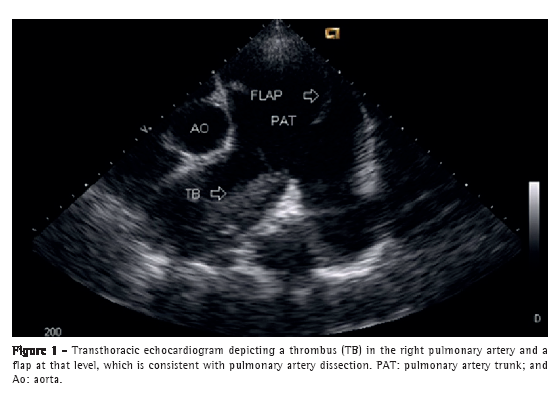

A 50-year-old male patient diagnosed four years prior with pulmonary hypertension related to schistosomiasis mansoni was admitted to the emergency room of the Federal University of Minas Gerais School of Medicine Hospital das Clínicas, located in the city of Belo Horizonte, Brazil. He presented with new onset, progressively worsening retrosternal chest pain and shortness of breath (functional class III pulmonary hypertension according to the World Health Organization). He had been diagnosed with chronic myeloid leukemia seven months prior and had since been on chemotherapy. At admission, transthoracic echocardiography revealed a large non-obstructive central thrombus in the right main pulmonary artery. The right atrium was dilated, and there was mild tricuspid regurgitation, with an estimated pulmonary artery systolic pressure of 63 mmHg. He was diagnosed as having in situ thrombosis as a complication of the long-standing pulmonary hypertension. After the possibility of acute coronary syndrome had been excluded, he was discharged on warfarin. He was re-admitted two months later due to progressively worsening, refractory chest pain. At that time, he had an SpO2 of 96%, and a third heart sound was audible at the lower left parasternal space, accompanied by a murmur of tricuspid regurgitation. The lungs were clear, and the peripheral arterial pulses were symmetric. Laboratory test results were unremarkable, including serum levels of creatine kinase, creatine kinase MB isoenzyme, and troponin. A resting electrocardiogram showed evidence of acute myocardial ischemia in the anterior leads. Transthoracic Doppler echocardiogram revealed a pulmonary artery systolic pressure of 62 mmHg, a thrombus in the right pulmonary artery, as in the previous examination, and the presence of a flap at that level that was compatible with pulmonary artery dissection (Figure 1). The diagnosis was confirmed by subsequent CT pulmonary angiography (CTPA; Figure 2). He was transferred to another cardiovascular treatment facility, where attempts were made to correct the defect with an endovascular procedure (via the femoral vein). During the perioperative period, the patient presented with refractory cardiogenic shock. Multiple efforts to resuscitate the patient were unsuccessful, and he died in the operating room.

To our knowledge, this is only the second report of a case of pulmonary artery dissection in a patient with schistosomiasis-related pulmonary hypertension, the first such case having been diagnosed at autopsy.(6) Clinically, these cases present with aggravation of previous symptoms of dyspnea and chest pain. The chest pain is typically sharp and can mimic acute coronary syndrome or acute aorta dissection. Cyanosis can be present.(7) The diagnosis is often obtained postmortem, because most patients die suddenly due to cardiac tamponade or severe pulmonary bleeding. If the diagnosis is made antemortem, the first finding is the emergence of a flap in the lumen of the dilated pulmonary artery or trunk formed from the intimal layer, denoting the entry tear into the false lumen but rarely an exit, which is the opposite of what is found in cases of aortic dissection.(8) Magnetic resonance imaging or CTPA of the chest can confirm the diagnosis and the associated complications, such as an increase in pulmonary artery dilatation, bloody pleural fluid, and pulmonary opacities.(1) The evolution is usually rupture of the vessel with blood flowing into the mediastinum, pericardium, or lung, because there is no exit from the false lumen. The intimal tear that leads to the dissection occurs at the point of greatest dilatation as a consequence of an increased parietal tension. It has been reported that inflammation due to in situ thrombosis can play a synergistic role in the development of the intimal disruption.(4,9,10)